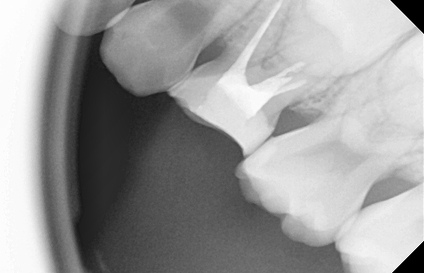

유치 신경치료는 유치에서 충치가 깊어져 치아 내부의 신경(치수)까지 감염되었을 때 시행하는 치료입니다.

먼저, 감염된 신경 조직과 염증을 제거하고 소독한 후, 신경조직이 있던 자리에 약을 채워 유치를 보존하는 술식입니다.

이를 통해 통증을 해소하고, 유치가 자연스럽게 빠질 때까지 제 기능을 할 수 있도록 도와줍니다.